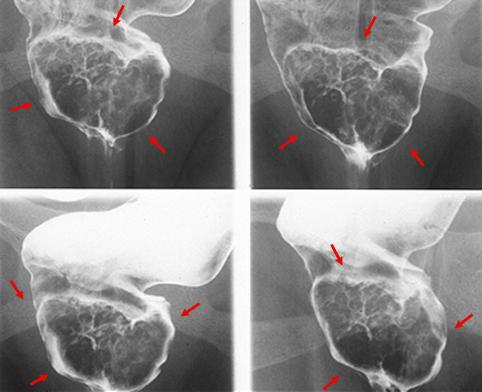

A case of rectal endocrine cell (small cell) carcinoma with a partial adenocarcinoma component.

Tokyo Pref., Cooperative study between National Cancer Center and Kyushu Cancer Center

Malignant epithelial tumor/Undifferentiated carcinoma

Large intestine(Colon)/Rectum

X-ray

Type 1 Protuberant (polypoed) type/

40 -

muscularis propria